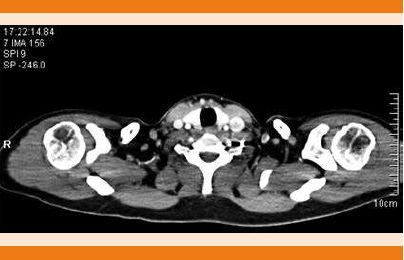

LA TAC de cuello y tórax simple y con contraste IV reportó ganglios de tipo inflamatorio en la región III y supraclavicular izquierdo y ganglios de tipo inflamatorio en la región axilar bilateral (Figuras 1 y 2). Durante su estancia intrahospitalaria tuvo fiebre de 38.3°C que cedió tras la administración de metamizol 1 g, se tomaron muestras de hemocultivo por punción directa que a los siete días de incubación se reportaron negativos.

Figura 2 Tomografía axial computada de tórax con contraste. Los tejidos blandos muestran imágenes ovoides hipodensas con hilio graso en ambas regiones axilares.

Los estudios de imagen (tomografía axial computada, imagen por resonancia magnética, tomografía computada por emisión de positrones) tampoco proveen un diagnóstico concluyente. Los hallazgos que se han relacionado con la enfermedad en tomografía incluyen: linfadenopatía múltiple homogénea que incluye niveles II a V, 94% son menores a 2.5 cm, con infiltración periganglionar y necrosis.15